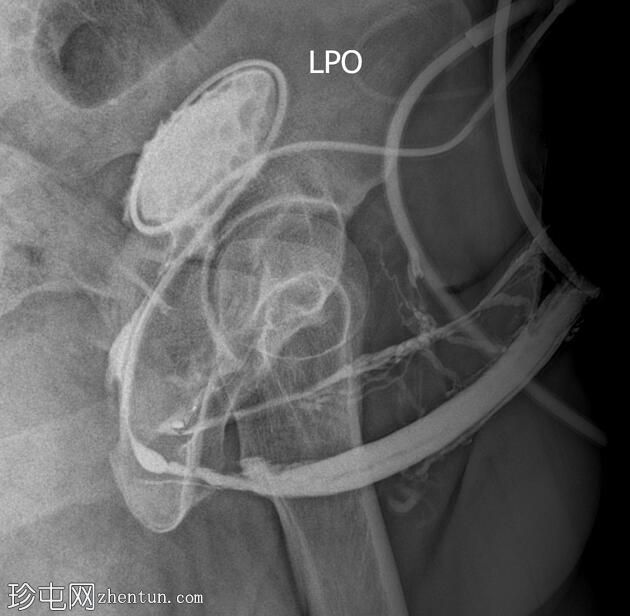

冠状位

斜位

逆行尿道造影显示球部近端尿道存在长段狭窄,造影剂广泛渗入阴茎静脉丛和盆腔静脉。

阴茎尿道外观正常。

造影剂已开始充盈膀胱。

该患者尿流细弱,表现为球部尿道长段狭窄。造影剂渗入与注射时施加的压力有关。